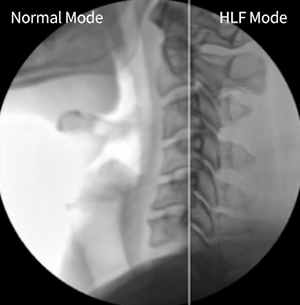

High-Level Fluoroscopy Mode

HLF Mode

High Powered HLF Mode produces high quality image with its uncomparable fluoroscopy and penetration than other standard C-Arms.